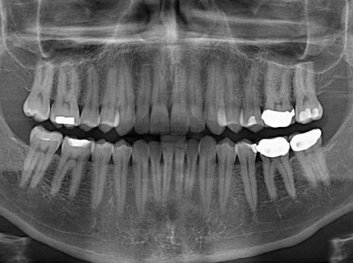

Adam Celiz,是來自諾丁漢大學(xué)的研究人員,他和同事開發(fā)的這種新型合成生物材料,能刺激干細胞在牙髓部的生長。與普通材料一樣,這種合成材料被填充到牙齒并用UV光硬化。

在體外測試中,材料刺激干細胞進入牙本質(zhì)的增殖和分化速度,促進形成牙齒骨組織。研究人員認為,一旦材料在受損牙齒中應(yīng)用,這些干細胞可以自動修復(fù)來自填充物上的損壞。在本質(zhì)上,該生物材料將使牙齒自愈。

在未來,Adam Celiz說,可再生材料能制成各種填充物以便受損牙齒的自身治愈,降低補牙失敗率,甚至?xí)蟛糠秩藢Ω苤委煹男枰?/p>